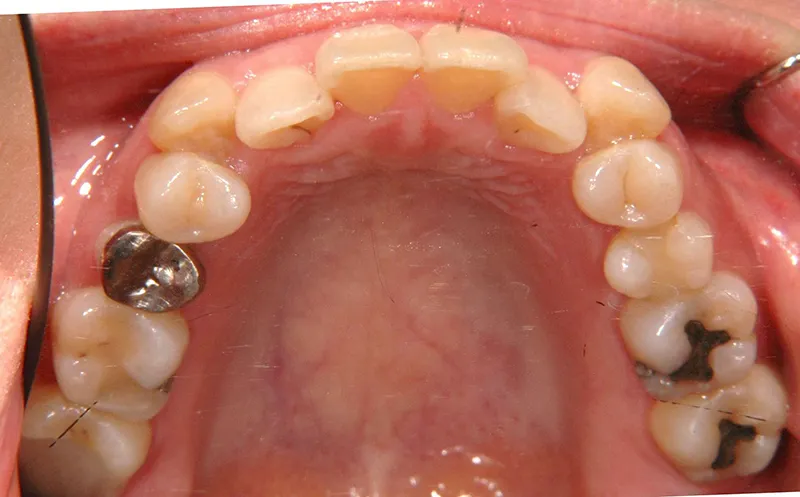

初診時年齢 40歳以上 (女性) 主訴 上下のがたがた・噛み合わない

診断名 叢生 装置名

特徴 ゆがんで生えている

状態 ガタガタ・でこぼこに生えている(叢生)

八重歯(叢生)

上下のがたがたと噛み合わない事を主訴に来院されました。

歯は抜かずに矯正治療しました。

初診